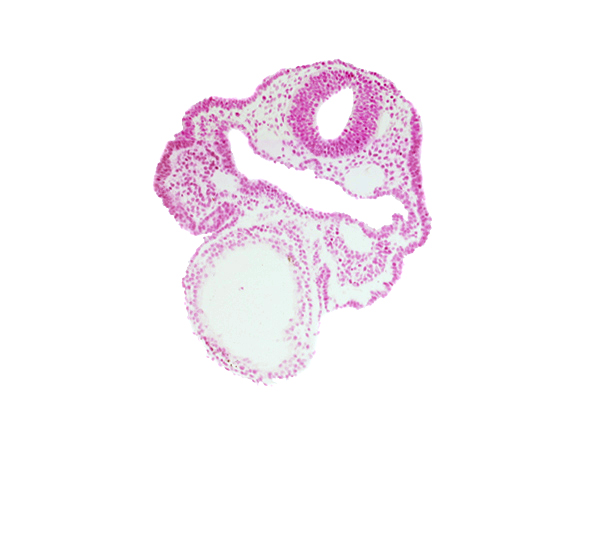

Carnegie Embryo #6344 | Location: 02-08-10

Keywords: aortic arch 1, cardiac jelly, dorsal aorta, epimyocardium, facio-vestibulocochlear neural crest (CN VII and CN VIII), notochordal plate, primary head vein, rhombencephalon (Rh. 4), surface ectoderm

Source: The Virtual Human Embryo.